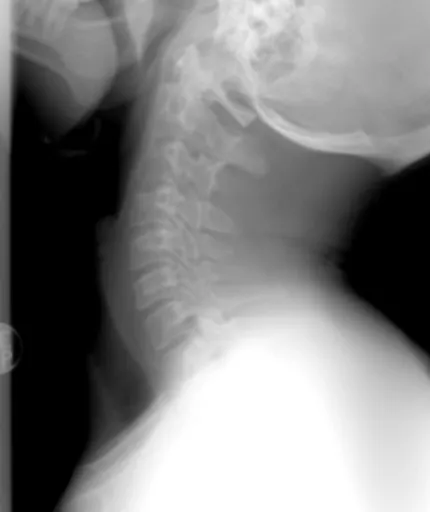

가장 대표적인 신경 압박 원인 중 하나가 바로 허리 디스크, 즉 추간판 탈출증이에요. 허리 척추뼈 사이의 디스크(추간판)가 제자리에서 밀려나와 주변 신경을 누르는 거죠. ** 이때 신경이 눌리는 위치에 따라 엉덩이부터 다리까지 뻗치는 통증이나 저림, 감각 이상이 나타날 수 있어요. ** 허리도 아프고 다리도 저리다면, 의심해 볼 만해요.

좌골신경은 우리 몸에서 가장 굵고 긴 신경 중 하나인데, 허리에서 시작해서 엉덩이를 지나 다리 뒤쪽으로 내려가요. 이 좌골신경이 어떤 이유로든 압박받거나 자극받으면 좌골신경통이 발생하는데, 이때 엉덩이에서 시작해 다리까지 찌릿찌릿하거나 타는 듯한 저림 증상이 나타날 수 있답니다. 오래 앉아 있거나, 허리에 무리가 가는 활동을 할 때 더 심해지기도 해요.